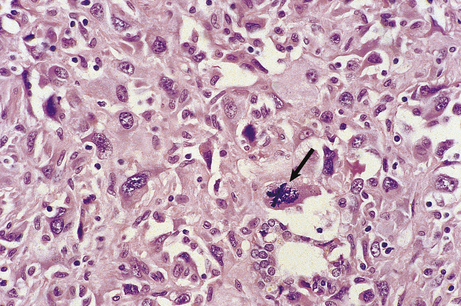

These features are often seen to their greatest degree in malignant neoplasms (Fig. 11.9).

image

Fig. 11.9 Histological features of neoplasia. A malignant neoplasm showing no immediately recognisable differentiated features, loss of cellular cohesion, and increased nuclear size and mitotic activity. Abnormal mitoses are present (arrowed).